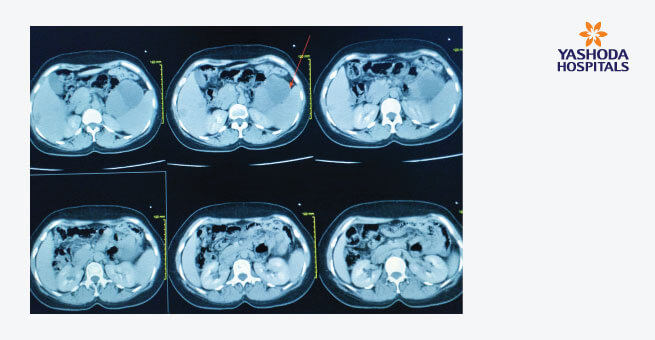

- A triphasic CT Scan or MRI is ordered to get a complete and detailed scan of the pancreas